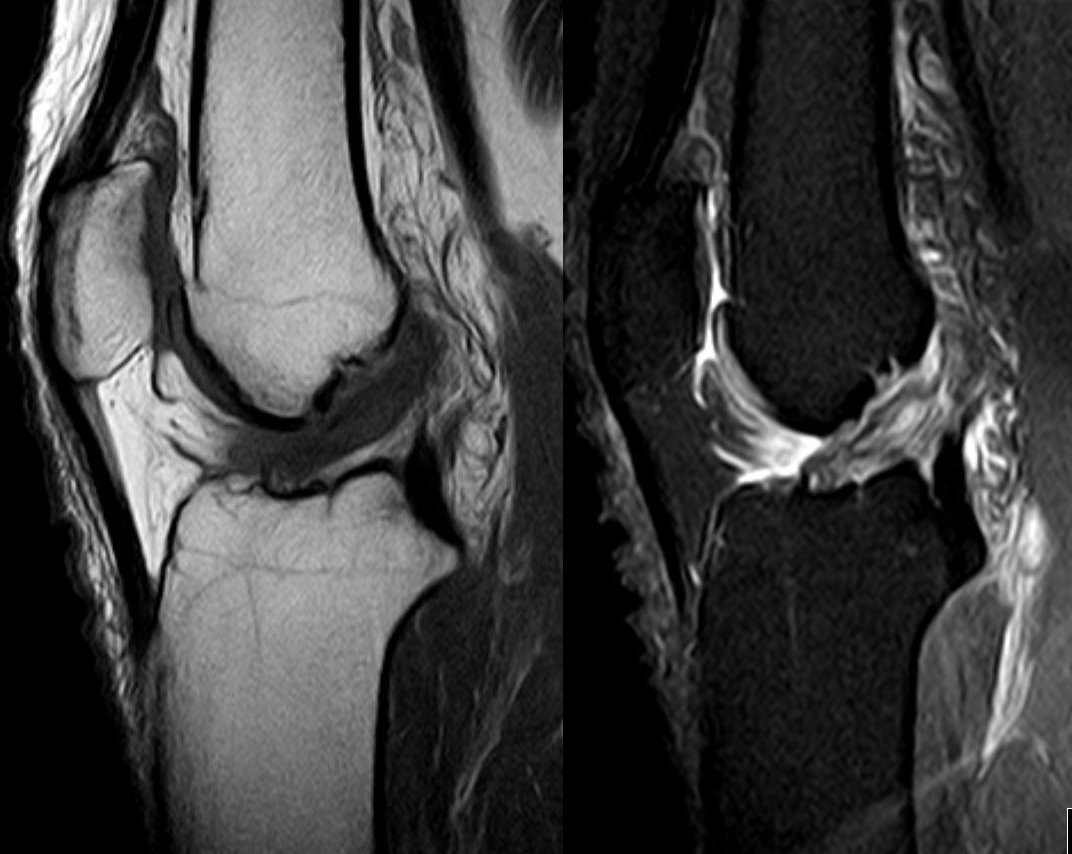

자기 공명 영상(MRI)은 인대, 연골 등 연부 조직의 손상을 확인하는 데 유용하며, 진단을 확진하는 데 사용된다.[2] MRI는 반월판 연골이나 측부 인대와 같이 함께 손상될 수 있는 다른 구조물도 보여준다.[31] X선 촬영은 골절 여부를 확인하기 위해 추가적으로 시행될 수 있다.[9]

MRI는 전방십자인대의 상태를 진단하는 데 가장 많이 사용되는 기술이지만, 부상 후 관절을 채우는 혈액 때문에 전방십자인대가 가려질 수 있으므로 항상 가장 신뢰할 수 있는 기술은 아니다.[32]